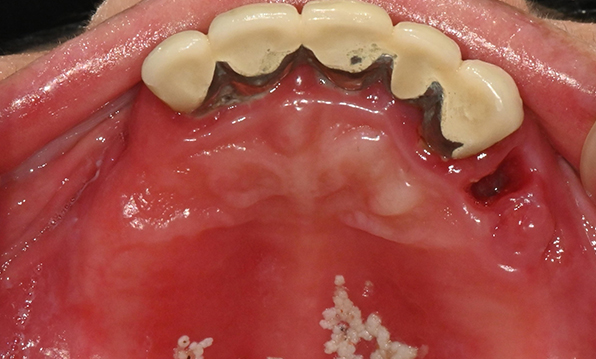

Before & After

Case 01

Before After